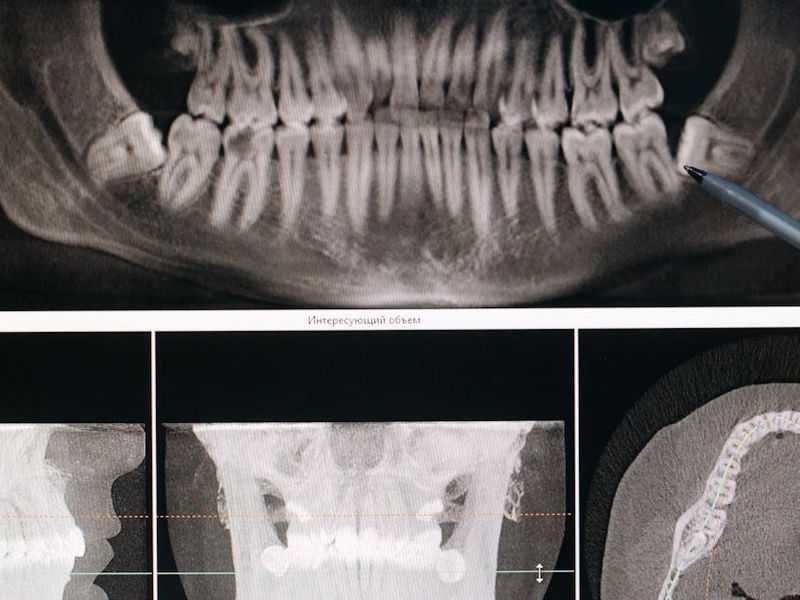

Cutting‑Edge Clinics and On‑Site Technology

Modern dental clinics in Cuenca are equipped with technologies that used to be limited to major U.S. centers: 3‑D CBCT imaging for precise bone and nerve mapping, digital intraoral scanners, CAD/CAM milling for same‑day crowns, and on‑site labs that speed up prosthesis fabrication. Many practices offer fully digital workflows—virtual planning, guided surgical guides and digital prosthetics—leading to predictable outcomes and shorter treatment timelines.

- Verify the technology: Do they use CBCT imaging, digital treatment planning and CAD/CAM systems?